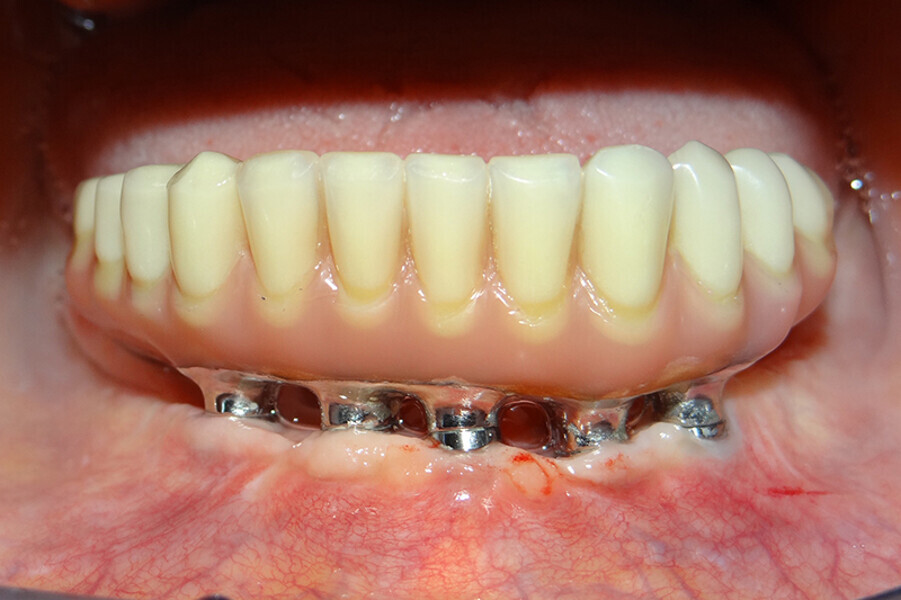

Fig. 4 Prótesis Híbrida inmediata y radiografía control con 6 años post-operatorio

Fig. 5. Prótesis Híbrida inmediata y radiografía control con 6 años post-operatorio

Fig. 6. Prótesis Híbrida inmediata y radiografía control con 6 años post-operatorio